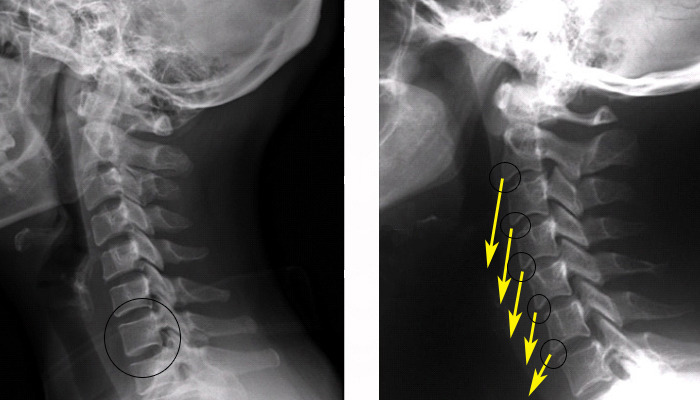

위의 그림에서 좌측 그림을 보시면 하단에 원이 그려져있는데 보통의 척추는 원형으로 되어있기때문에 정상적일 경우에 측면에서 사진을 찍어보면 직사각형의 모습을 하고 있습니다. 그러나 목을 앞으로 빼는 자세 - 컴퓨터를 보거나 하는 자세, 힘을 써서 일을 팔로 하는 경우 등등에 있어서 - 를 하게 되면 목 앞쪽의 흉골과 경추를 연결하는 근육과 scm이 단축되기 때문에 시간이 흐를수록 정상적인 C 자 곡선의 경추뼈가 일자목으로 변해가게 되며(좌측그림), 뼈의 형상도 측면에서 촬영시 직사각형이 아니라 우측 그림에서 보이듯이 뼈도 모서리가 뾰족해지는 형상으로 변하게 됩니다.  나이가 들어가시면 생활습관과 태도등에 의해서 골막이 변하기 시작하며, 혹은 협착이 생기기도 하여 경추병이 발병하게 됩니다.

아래의 사진을 보시면서 설명을 이어나가도록 하겠습니다.  먼저 뼈를 살펴보면 C1 부터 C7 까지가 일자로 되어있는 것을 보실수 있습니다. 일자목이 되게되면 환자분이 젊은 나이의 경우에 별다른 통증을 못 느끼는 경우도 종종 있습니다만, 대체적으로 목과 어깨쪽의 불편한 증상을 느끼게 됩니다.

이런 경우에는 목을 일자상태에서 다시 C 자 커브를 이룰 수 있도록 교정해주는 작업이 필요하다 하겠는데, 침만으로 어떻게 증상이라도 완화하는 것을 기준으로 설명을 하도록 하겠습니다.

먼저 좌측의 노란 화살표에서 보시다시피, 경추에 붙어있는 근육들이 단축되어서 경추뼈에 골막을 형성하여, 뼈끝이 뾰족하게 변한 것을 보실 수 있습니다. 이러한 변화는 1-2년에 이뤄지는 것이 아니고 최소 수년에서 수십년에 걸쳐서 일어나는 변화입니다.

일자목 상태이므로 목이나 어깨쪽의 피로가 남들보다는 빠르게 나타났을 것임을 예측해볼 수 있는데, 보통은 그저 가볍게 뒷목을 두들기거나 주물러주거나 하는 식으로 넘어가기도 하고, 한약등을 복용하면 어깨 통증이 말끔해지기도 합니다.

이 사진의 주요한 변증포인트는 일자목으로 인한 경항부의 불편함과 특히 C6-C7 의 협착으로 인한 어깨, 팔통증을 예측할 수 있습니다. C6 이 목경직과 상박부통증, C7 이 등쪽 통증을 수반하게 됩니다. 또한 신경의 체절분포에 따라 C6-7번 영역에 해당되는 부위의 병증이 나타납니다. 주로 어깨나 손가락의 저림, 감각이상등입니다.